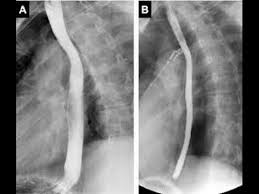

Diffuse Esophageal Spasm Wikipedia